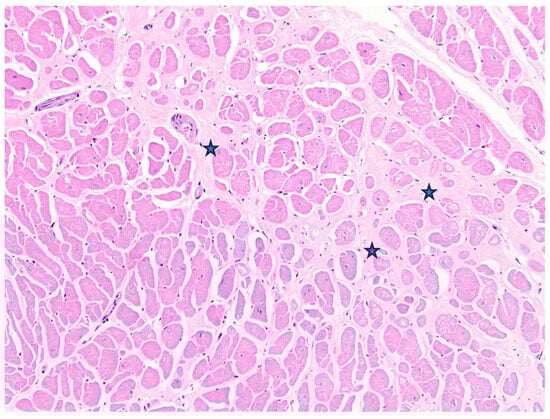

Case 2 was a 21-year-old female zoo-housed Matschie’s tree kangaroo weighing 8.69 kg. This geriatric kangaroo was euthanised due to deterioration of chronic vertebral osteoarthritis that had been managed with non-steroidal anti-inflammatory medication for the previous three years. At postmortem examination, the right ventricle was subjectively thin-walled and flaccid. The lungs oozed serous fluid on the cut section, and there was serosanguinous fluid in the large airways and pericardial sac. The (LV+S)/RV was elevated above reference values; however, HW/BW% was within the reference values. For ventricular wall ratios, LV:RV was elevated and RV:S decreased, suggesting left-side ventricular hypertrophy and/or thinning of the RV wall. Microscopically, there was moderate cardiomyocyte hypertrophy in the left ventricle, with multifocal interstitial myocardial fibrosis, myofiber degeneration, loss, and atrophy, with interstitial oedema (Figure 3). The lungs were diffusely congested, airways often flooded by proteinaceous fluid, with diapedesis and increased foamy macrophages, and haemosiderophages were not observed.

Figure 3. Case 2, Matschie’s tree kangaroo (D. matschiei), left ventricular myocardium, haematoxylin and eosin stain. Cardiomyocytes are hypertrophic with increased variation in size. Mature fibrocollagenous connective tissue dissects between and isolates individual fibres (stars).

In Case 2, elevated (LV+S)/RV and LV:RV, and decreased RV:S, provided supportive evidence for left ventricular hypertrophy and left-sided congestive heart failure, alongside corroborative findings of myocardial hypertrophy with myofiber degeneration, and interstitial fibrosis, pulmonary oedema, and serous pericardial effusion. These findings were consistent with expected lesions in hypertrophic cardiomyopathy of felids and other domestic species [30]; however, HW/BW% was not increased in Case 2. For Case 1, elevated LV:RV lent further weight to grossly observed RV thinning and probable right-sided congestive heart failure, supported by chronic passive congestive and fibrotic changes in the liver and ascites observed grossly. Histopathological findings in the liver mirrored expected lesions in domestic animals with chronic right-sided congestive heart failure [30,31]. Hypertrophic cardiomyopathy has been previously described in two captive Bennett’s wallabies [17]. Although body and heart weights were not published, reported (LV+S)/RV values of 5 and 8.2, for each wallaby, respectively, were elevated above the reference values determined in this study, lending further support for HCM in these individuals. Conversely, LV:RV, LV:S, and RV:S were within the RI generated here. Other reports of cardiomyopathies in macropods reviewed during this study did not include sufficient information to allow assessment of hearts against generated reference values. Future studies will benefit from larger sample sizes and expansion of the number of species examined.